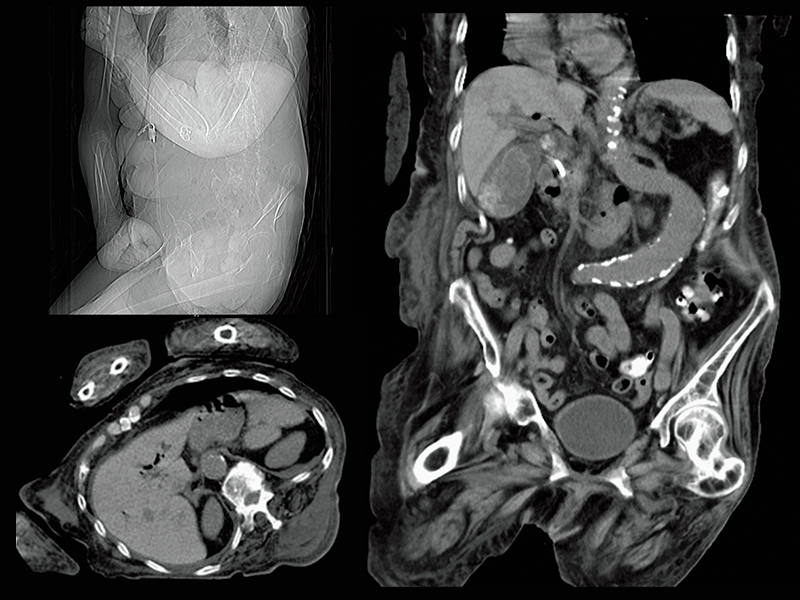

Abdominal aortic occlusion

Intraoperative oxygen desaturation(Left)

Left common iliac artery occlusion(Right)